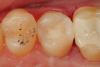

Fig 10. A preoperative occlusal view of tooth Nos. 18 and 19 with composite restorations that are exhibiting marginal breakdown.

Figure 10